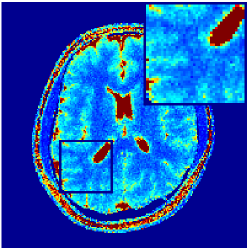

Two sets of experiments were conducted here: first, we used the 2D and 3D acquisition sequences for scanning a healthy volunteer’s brain (real-world acquisitions). Figures 6 and 7 display the parametric maps reconstructed from 2D spiral and radial readouts. We computed the T1, T2 and proton density (PD) maps using baseline reconstruction algorithms ZF, VS, LR, FLOR, AIR-MRF and our proposed LRTV. While baselines use DM either for quantitative inference or also during reconstruction (i.e. AIR-MRF), we further compare the DM-free LRTV’s performance when cascaded to DM, KM and MRFResnet for quantitative inference. For the 3D spiral acquisitions we compared LRTV and its closest competitor VS in Figure 8. Outcomes from other tested algorithm are displayed in the supplementary materials (Figure S5). Since FLOR does not use dimensionality-reduction, our system ran out of memory during 3D reconstruction; hence results are not reported in this case.

VI-E1 Discussion

The LRTV-DM and LRTV-MRFResnet perform on par, and both outperform all tested baselines for reconstructing T1, T2 and PD maps in all acquisition schemes. This can be observed both visually in Figures 6, 7, 8, S2 and S3, and quantitatively in Table IV across all tested metrics. Other baselines were unable to successfully remove the under-sampling artefacts in TSMIs, and these errors propagated to the parameter inference phase and resulted in inaccurate maps. Temporal-only priors incorporated within LR are shown insufficient to regularise the inverse problem and LR sometimes (e.g. 2D spiral acquisitions) can admit solutions with even stronger artefacts than the model-free ZF baseline. This issue was previously studied for other non-Cartesian MRF readouts that similar to our spiral/radial trajectories, miss to sample the corners of the k-space in all timeframes (see section 2.2.2 and figure 2 in [19]). In the absence of reference for the k-space corners information, the LR iterations despite minimising the objective can converge to solutions with high-frequency artefacts, as visible in the computed maps. This highlights the need for adding an appropriate spatial-domain regularisation. FLOR reduces the LR’s artefacts but this improvement is limited because the suggested nuclear norm penalty does not incorporate an explicit spatial regularisation. Further for reducing artefacts, FLOR can introduce an undesirable bias in the computed T1/T2 maps e.g. see error maps in Figures S2 and S3. The non model-based VS baseline incorporates spatial regularisation and results in spatially smoother maps than ZF and LR, but it is unable to output artefact-free images. Further and consistent with our in-vitro experiment, we observe that VS overestimates the T2 values (e.g. in White and Grey matter regions) in tested 2D acquisitions i.e. the spatial regularisation trades off agains the quantification accuracy. The model-based AIR-MRF adds spatial regularisation through 2D/3D low-pass Gaussian filters however this trades off the sharpness of the computed maps and can increase the errors at the tissue boundaries (we searched Gaussian spreads that keep the blurs and high-frequency artefacts minimal). For our acquisition readouts, Gaussian filters performed better than disk filters of [19] for avoiding strong Gibbs artefacts. On the other hand, the spatiotemporally regularised LRTV greatly improves the TSMI reconstructions i.e. 4 dB enhancement compared to the closest competitor baseline (Table IV). This enables computing accurate and aliased-free multi-parametric inference using DM or the DM-free learning-based alternative MRFResnet as visible in Figures 6, 7, 8, S2 and S3. MRResnet and DM score competitive quantitative inference results i.e. T1 and T2 MAPE less than 5% and 9%, respectively (Table IV). KM also outputs comparably accurate T1 maps, however this shallow learning model despite having a model size larger than MRFResnet, is unable to learn accurate T2/PD quantification and it results in poor estimated maps, consistent with our observations in section VI-C.